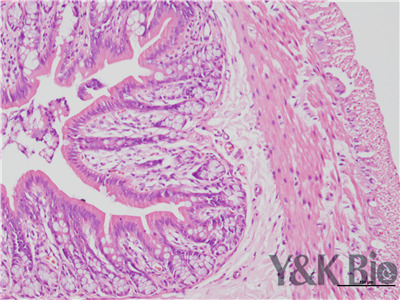

HE染色流程是什么,很多人都不知道,今天跟着小编一起来学习一下,切片的好坏直接影响疾病诊断的及时与准确性。因此一张高质量的HE染色切片,是实验室必须掌握的技术之一。HE染色目前在国内国外病理诊断上被

广泛采用,常规的染色方法。下面一起来看HE染色的基本顺序。一般切片的片子应在60-70度左右的烤箱中烘烤30分钟以才可以进行染色。总的来说是一个时间较长的过程。

1.样品制备

对于贴壁生长细胞,胰酶消化,调整细胞浓度约1×105/ml,滴加于盖玻片上(置于6孔板中),培养相应时间后,取出细胞爬片,用PBS 洗涤3次。2.样品固定 95%乙醇固定20min,PBS洗涤2次,每次1min。3.染核 苏木

素染液染色2-3min,自来水洗涤。4.分色 镜下观察,若细胞核染色过深,用1%盐酸酒精溶液分色数秒,自来水洗涤。 5.染胞质 浸入伊红染液染色1min,自来水洗涤。6.封片 吹干或自然晾干细胞爬片后,吉林中性树胶封片。

以上六点就是HE染色的基本步骤,大家可以参考一下哦 。